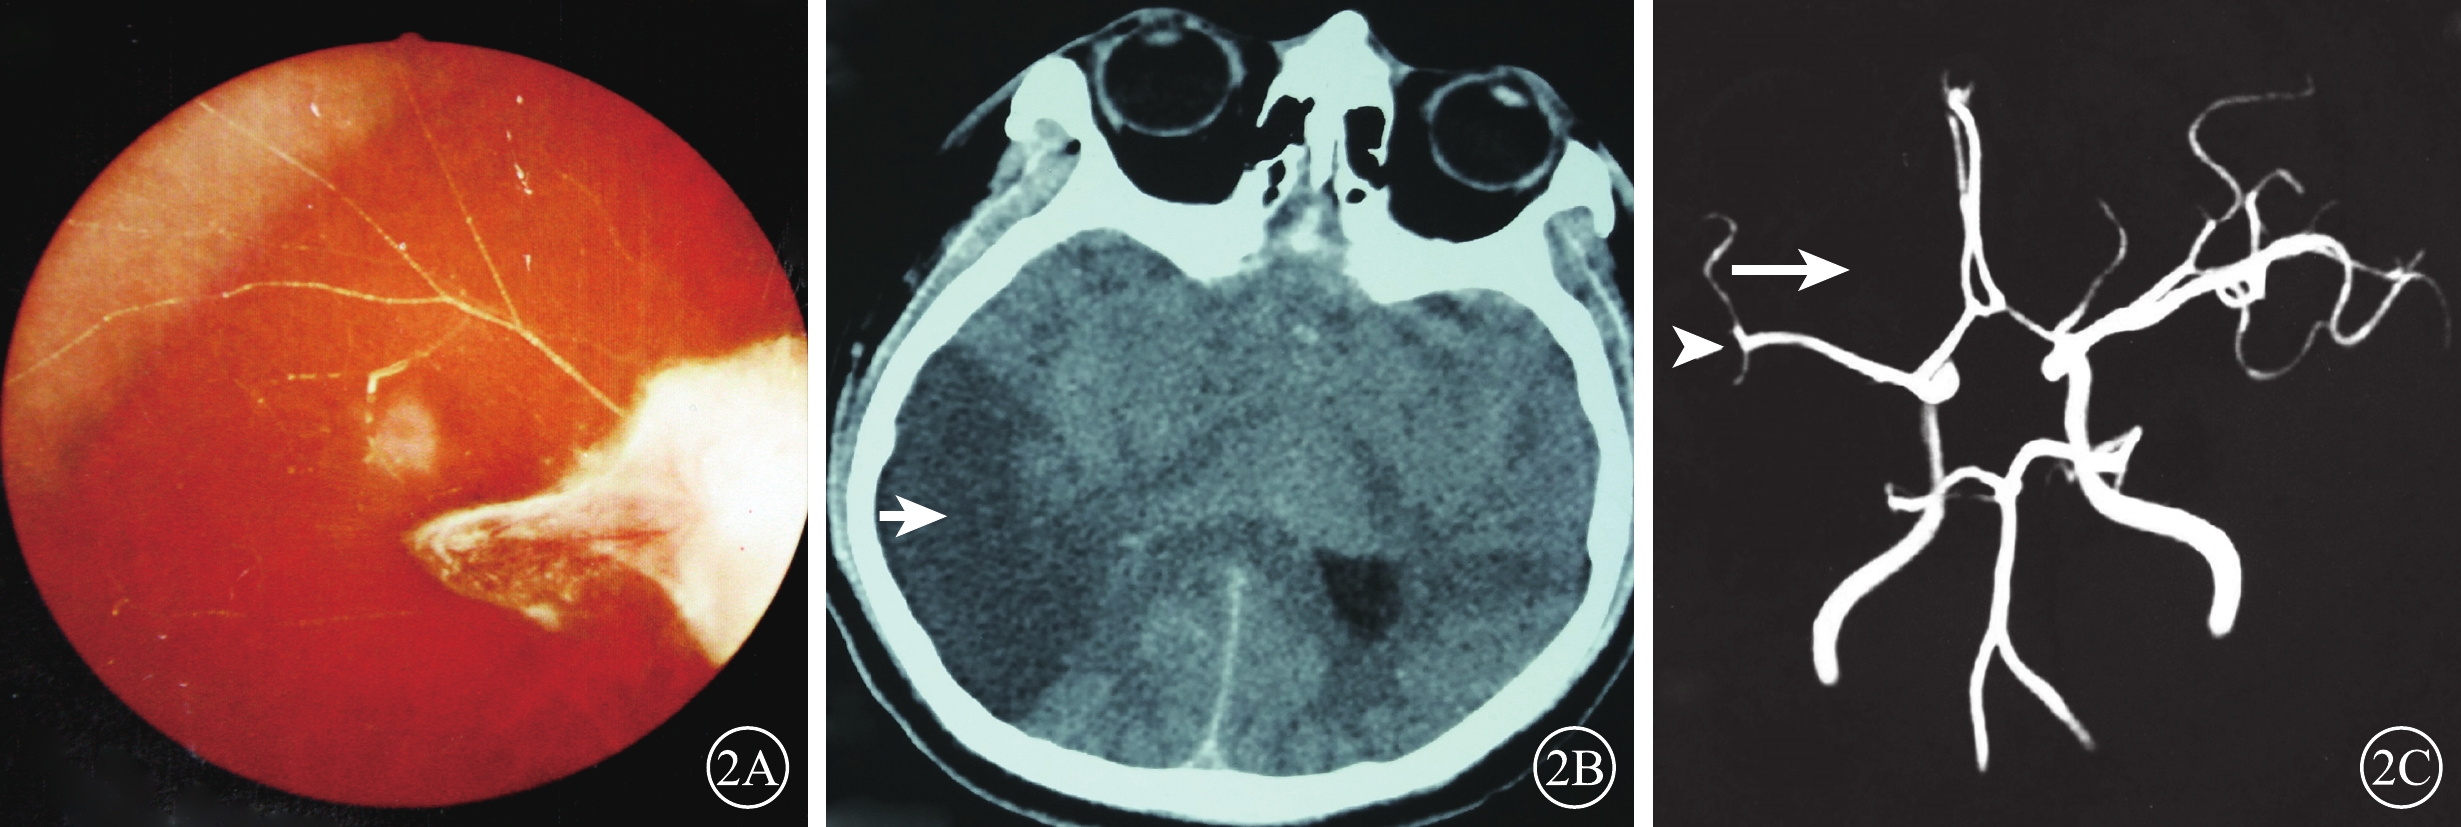

患眼視力無光感~0.6。20只眼中,單純OAO 3只眼(15%);OAO合并CAO 4只眼(20%)、MAO 1只眼(5%);單純RAO 7只眼(35%),其中CRAO(圖1)、HRAO、BRAO分別為4、1、2只眼;CRAO伴PCAO 1只眼(5%);PCAO伴NAION 1只眼(5%);CRAO合并DNAO 2只眼(10%);CRAO、PCAO合并右大腦中動脈阻塞1只眼(5%)(表2)。20例中,眼球運動障礙和眼瞼皮膚發紺4例(20%);合并面部疼痛、鼻部皮膚缺血壞死2例(10%)。顱腦CT檢查示右側大腦中動脈供血區域低密度缺血灶1例(20%)。MRA檢查發現顱內新發缺血灶6例(30%)。6例患者中,玻尿酸注射者5例,均為無癥狀的小血管阻塞。自體脂肪注射者1例,男,27歲。右眼視力無光感,眼球運動障礙;左側肢體偏癱。眼底可見后極部灰白色水腫,黃斑中心凹反光消失(圖2A);顱腦CT檢查,右側顳葉低密度梗死灶(圖2B);MRA檢查,右側眼動脈未顯影,大腦中動脈M2段閉塞(圖2C)。

圖2

序號7患者彩色眼底、CT、MRA像。2A示右眼彩色眼底像,顳上血管白線狀,其余血管消失;視盤結構不清,其顳側灰白色極化灶。2B示CT像,右側顳葉低密度梗死灶(白箭);2C示MRA像,右側眼動脈未顯影(白箭),大腦中動脈M2段閉塞(白箭頭)

圖2

序號7患者彩色眼底、CT、MRA像。2A示右眼彩色眼底像,顳上血管白線狀,其余血管消失;視盤結構不清,其顳側灰白色極化灶。2B示CT像,右側顳葉低密度梗死灶(白箭);2C示MRA像,右側眼動脈未顯影(白箭),大腦中動脈M2段閉塞(白箭頭)

患眼視力無光感~0.6。20只眼中,單純OAO 3只眼(15%);OAO合并CAO 4只眼(20%)、MAO 1只眼(5%);單純RAO 7只眼(35%),其中CRAO(圖1)、HRAO、BRAO分別為4、1、2只眼;CRAO伴PCAO 1只眼(5%);PCAO伴NAION 1只眼(5%);CRAO合并DNAO 2只眼(10%);CRAO、PCAO合并右大腦中動脈阻塞1只眼(5%)(表2)。20例中,眼球運動障礙和眼瞼皮膚發紺4例(20%);合并面部疼痛、鼻部皮膚缺血壞死2例(10%)。顱腦CT檢查示右側大腦中動脈供血區域低密度缺血灶1例(20%)。MRA檢查發現顱內新發缺血灶6例(30%)。6例患者中,玻尿酸注射者5例,均為無癥狀的小血管阻塞。自體脂肪注射者1例,男,27歲。右眼視力無光感,眼球運動障礙;左側肢體偏癱。眼底可見后極部灰白色水腫,黃斑中心凹反光消失(圖2A);顱腦CT檢查,右側顳葉低密度梗死灶(圖2B);MRA檢查,右側眼動脈未顯影,大腦中動脈M2段閉塞(圖2C)。

圖2

序號7患者彩色眼底、CT、MRA像。2A示右眼彩色眼底像,顳上血管白線狀,其余血管消失;視盤結構不清,其顳側灰白色極化灶。2B示CT像,右側顳葉低密度梗死灶(白箭);2C示MRA像,右側眼動脈未顯影(白箭),大腦中動脈M2段閉塞(白箭頭)

圖2

序號7患者彩色眼底、CT、MRA像。2A示右眼彩色眼底像,顳上血管白線狀,其余血管消失;視盤結構不清,其顳側灰白色極化灶。2B示CT像,右側顳葉低密度梗死灶(白箭);2C示MRA像,右側眼動脈未顯影(白箭),大腦中動脈M2段閉塞(白箭頭)